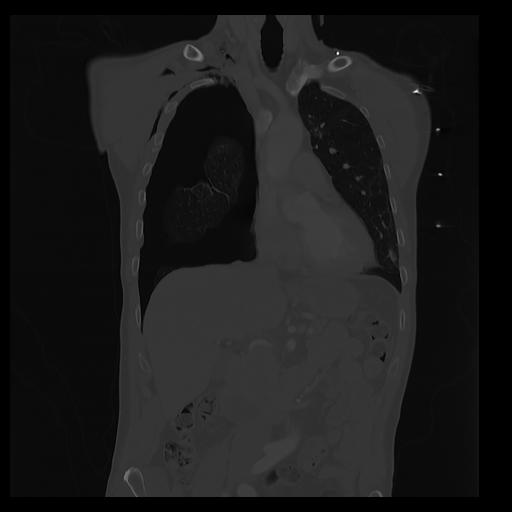

32 PULMON,CE,Coronal,3.000,PULMON,Coronal,